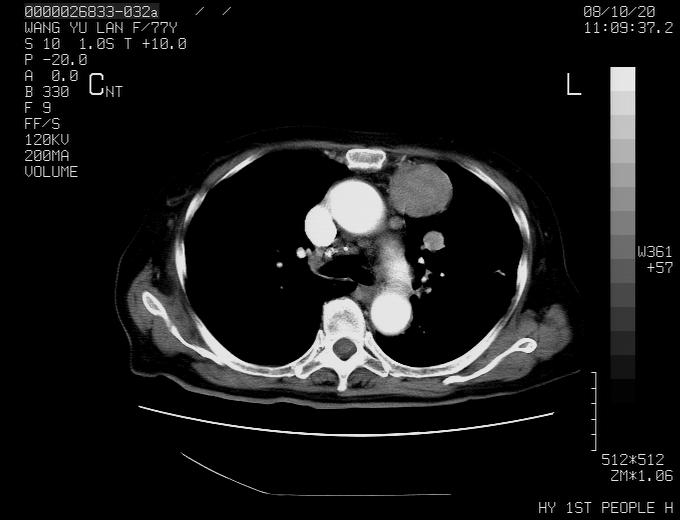

女性,77岁,胸部疼痛半月。左上肺团块影,本人考虑血管畸形,请分析

动脉期未见大血管同步强化,首先考虑周围型肺癌

动脉期病灶近中线侧可见星芒状与大血管同等强化密度,支持考虑血管畸形伴血栓形成,动脉期不曲型,不除外周围型肺癌

1、考虑avm可能性大。2、纵隔有肿大淋巴结,左肺上叶有炎性病变,不排除肺癌并转移可能。